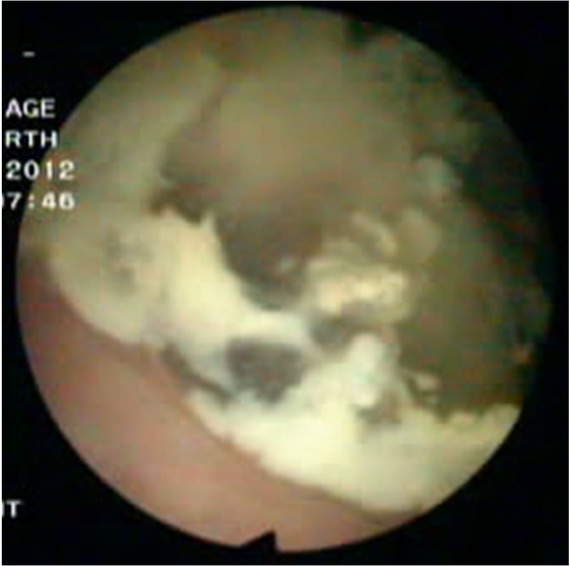

A 54-years old man with a 6-month history of intermittent episodes of irritative voiding symptoms of the bladder and weight loss was admitted. The patient did not have any gastrointestinal symptoms such as pain, obstruction or melena, and he presented a negative medical history for gastrointestinal diseases. The physical examination was negative. An urine analysis revealed 30 white blood cells and 12 red blood cells per high power field. No malignant cells were observed in the urine. The carcinoembryonic antigen level was normal. The enhanced pelvic computed tomography (CT) scan revealed an irregular and slightly higher density (Figure 1), with the largest cross-section of 5.2 cm×4.8 cm. Its CT value was slightly higher than the intravesical CT value. There was some punctate calcification on the edge and inside the hyperdense area. A cystoscopy showed an edematous broad opening with mucinous components in the right posterior wall of the bladder (Figure 2).

Cystoscopy findings. Cystoscopy was performed and an edematous broad opening with mucinous components in the right posterior wall of the bladder was observed.